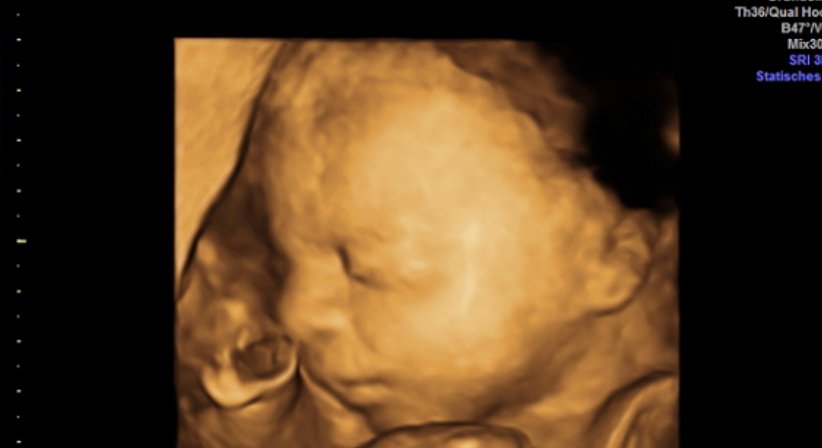

Wir verfügen seit 2015 über ein extrem hochwertiges Ultraschallgerät, das neben einer sehr guten Bildauflösung Techniken wie 3D Ultraschall, 4D Ultraschall und verbesserten Dopplerultraschall bietet. Ich selbst bin für diese Techniken sowie die Nackenfaltenmessungen (in der Frühschwangerschaft) zertifiziert. Bilder und Filme werden auf Wunsch auf einen USB-stick gespielt, sodass man diese mit nach Hause nehmen kann.

Mit verschiedenen Methoden können wir heute beurteilen, ob während der Schwangerschaft mit Mutter und Kind alles in Ordnung ist, oder ob Risiken vorliegen. Der Ultraschall hilft uns dabei als nahezu einzige Methode, das ungeborene Kind in der Gebärmutter direkt sichtbar zu machen.